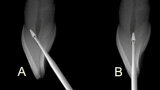

Fig. 5: In anterior teeth, the canal orifice is typically located just lingual to the incisal edge in incisors and the cusp tip in canines (middle) or directly under the incisal edge or cusp tip (right).

Fig. 6: A potential problem when attempting to access the orifice in anterior teeth is an approach at the middle of the lingual surface with an angle not following the root’s long axis that can lead to perforation of the tooth on the facial cervical (A), and the bur being used for access should be kept parallel to the roots long axis which often places the orifice under the incisal edge (B).